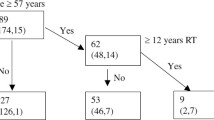

Analysis of influencing factors of moderate and severe vascular abnormalities after radiotherapy

Considering the clinical importance of moderate or high vascular stenosis in practice, patients in Group 2 were categorized into normal and abnormal groups based on their vascular conditions. Both groups were examined for general conditions, treatment factors, and factors affecting traditional atherosclerosis. The findings revealed that the age at revisit over 45 years, T stage, and N stage were significant influencing factors (Table 9).

In addition to the radiation itself and the time interval after radiotherapy, the radiotherapy dose may also affect CAS. However, the findings from various studies have diverged on this matter. Previous studies have shown that radiation injury to large and medium blood vessels has a dose-dependent effect (Dorth et al. 2014). Conversely, other studies have demonstrated that the dose of vascular damage caused by radiation has a certain threshold and that there is no dose effect within the dose range in patients with head and neck tumors receiving radiation (Martin et al. 2005). Steele et al. did not observe a definitive correlation between cumulative radiotherapy dose and CAS severity (Steele et al. 2004). Previous investigations examining the impact of the radiotherapy dose on vascular injury in large and medium arteries within the standard therapeutic dose range for head and neck treatment using conventional or IMRT have yielded inconclusive results (Cheng et al. 2000; Li et al. 2010; Huang et al. 2013; Zhou et al. 2015). The current study also failed to establish a correlation between the radiation dose and vascular injury. The limited sample size or delayed response of the blood vessel itself may have accounted for the failure to observe a dose-dependent effect within the designated observation period. Prolonged follow-up is necessary to investigate the time-dependent nature of carotid artery lesions. Furthermore, the effect of traditional atherosclerotic factors on CAS after radiotherapy remains unclear. Lam et al. (2001) determined that there was no significant association between post-radiotherapy carotid artery injury and conventional factors influencing atherosclerosis, whereas Dorresteijn et al. (2002) established that hypertension was associated with an increased risk of ischemic stroke in patients after radiotherapy. The results of our study indicated that carotid artery injury is associated with the existing age, T stage, and N stage. The P value of the impact of blood lipid levels and time elapsed after radiotherapy on CAS was found to be very close to 0.05, which is potentially attributable to the limited sample size. The risk factors for radiation therapy cannot be altered in patients with NPC. However, conventional atherosclerotic factors and the duration of radiation therapy can be promptly identified and addressed through regular monitoring. Consequently, patients with NPC should undergo carotid artery ultrasound screening 3 years after radiotherapy, and even if there is no obvious CAS, the development trend can be predicted by intima thickening and plaque status.